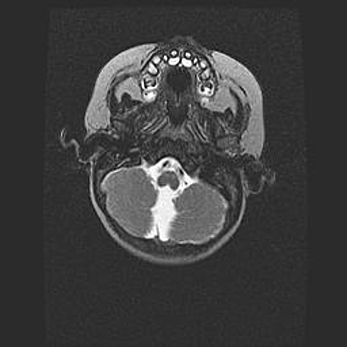

Мальформация Денди-Уокера. Киста задней черепной ямки.

Агенезия мозолистого тела.

Возраст: 2,5 месяца

Вес: 2420 г

Пол: женский

Окружность головы: 37 см

Срок гестации: 32 недели

Мальформация Денди—Уокера — редкий вид патологии ЦНС, представляющий собой врожденный порок развития каудального отдела ствола и червя мозжечка, ведущий к неполному раскрытию срединной (Мажанди) и латеральных (Лушка) апертур IV желудочка мозга. Для этогно синдрома характерна триада симптомов: гипотрофия червя мозжечка и/или полушарий мозжечка, кисты задней черепной ямки, гидроцефалия различной степени. В 70% случаев порок сочетается и с другими аномалиями головного мозга, в частности с агенезией мозолистого тела.